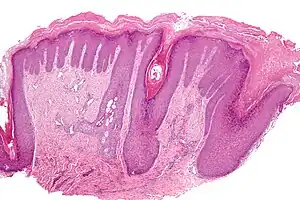

A hiperqueratose é o espessamento do estrato córneo (a camada mais externa da epiderme), muitas vezes associada com a presença de uma quantidade anormal de queratina[1] e também geralmente acompanhada por um aumento na camada granular.

A hiperqueratose folicular (também chamado frinodermia) é uma condição da pele caracterizada pelo desenvolvimento excessivo de queratina nos folículos capilares, o que resulta em pápulas elevadas em forma de cone. As aberturas são frequentemente fechado com um tampão de sebo incrustado.